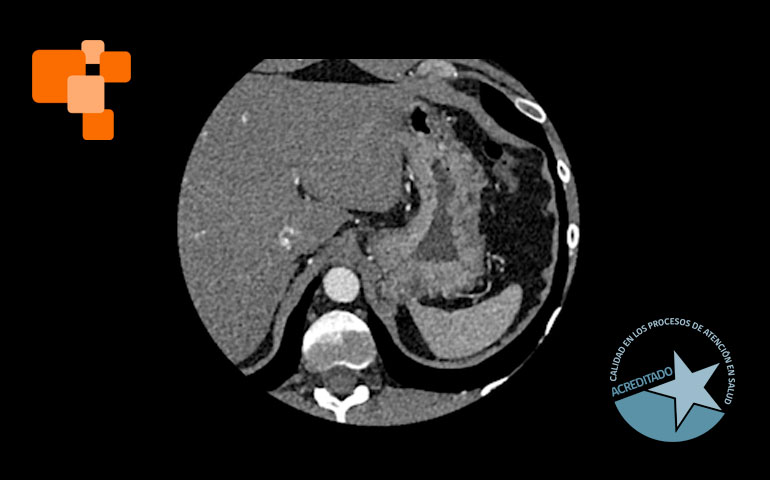

El TAC de calcio coronario es un examen de alta complejidad, realizado usualmente en centros de imagenología avanzada, mide el calcio en las arterias coronarias para evaluar el riesgo de eventos cardíacos futuros. Al proporcionar un score de calcio coronario, permite a los médicos identificar la acumulación de calcio y ajustar tratamientos para prevenir la aterosclerosis, una causa principal de ataques cardíacos. Según expertos, médicos especialistas en cardiologías lo sugieren principalmente para aquellos en riesgo moderado, pacientes que no han tenido síntomas, pero poseen factores de riesgo como hipertensión o colesterol alto.

La tomografía computada para el cálculo del score de calcio coronario permite identificar y cuantificar calcificaciones antes de que se manifiesten síntomas de enfermedad cardíaca, facilitando intervenciones tempranas. Es una técnica de diagnóstico por imagen que, a diferencia de otros métodos más invasivos, ofrece una evaluación rápida y no invasiva de las coronarias.

La elección de un centro de imagenología avanzada es crucial para asegurar la precisión del TAC de calcio coronario. En Centro de Diagnóstico San Lorenzo, nuestra infraestructura se encuentra equipada con la tecnología más avanzada, un TAC de 128 canales con inteligencia artificial, y todo un personal calificado que garantizan la calidad y fiabilidad de los resultados, aspectos fundamentales para un diagnóstico y tratamiento adecuado que recomendará su médico de cabecera.